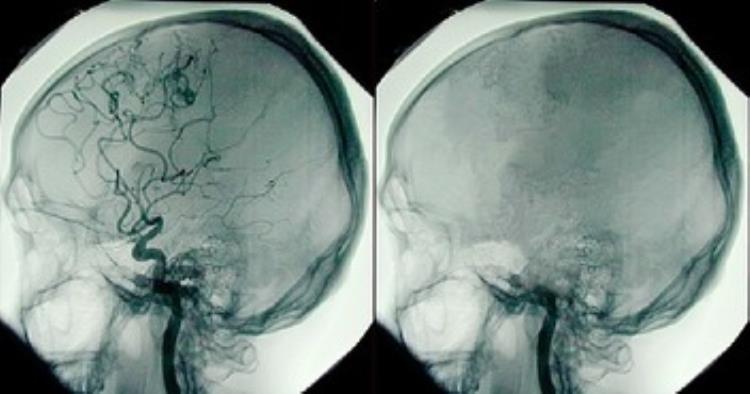

区别:脑死亡不同于“植物人”。脑干功能存在于“植物人”中。昏迷只由大脑皮层严重受损或突然抑郁引起。患者可以有自主呼吸、心跳和脑干反应。脑死亡是一种无自主呼吸的永久性和不可逆的死亡。植物人的脑电图(EEG)是分散的,而脑死亡的脑电图(EEG)只有一条线。